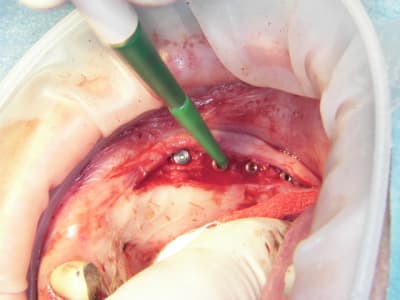

et puis alors??? on a un confrère qui s'éclate dans son travail et qui nous communique sa joie, en plus de photos qui nous apprennent beaucoup sur sa technique....c'est mieux que des posts du genre "j'en ai mare" ou " je flippe" ou encore "donnez moi une corde pour que je me pende..." , non???

pxav fait partie de ceux là...il nous en à fait à plusieurs reprises la démonstration avec ses techniques d'expansion osseuses extrêmement intéressantes...

15/07/2009 à 21h13

Pose d'implant court ce qui n'est pas ma tasse de thé, mais il ne faut pas mourir idiot, alors.

Un 103.4, un 6.5x4.6, un 8x4.6 et un 8x3.4

Première pour moi avec le nouvel Axiom d'Anthogyr.

Je n'étais pas sur de pouvoir utiliser la technique avec implant lisses, mais si.

Implants légèrement coniques, autoforants, outils trilobé et non pas 8 pans creux.

Pas eu de problèmes particuliers, il faut attendre pour le résultat.

Seul point il faut faire attention au vissage qui conditionne la position du cône morse.

Globalement j'ai bien aimé, même si je n'ai pas été aussi fabuleusement génial que d'ab dans la réalisation..........

Merci pour cette expérience partagée. Belles photos. Merci aussi d'avoir l'honnêteté de présenter un cas qui ,s'il paraît franchement parfait sur les photos de chir, l'est un poil moins sur la pano (mais c'est qu'une pano). De toute façon avec une expérience comme la tienne la gestion prothétique se fera sans doute sans trop de soucis.

Sympa aussi l'utilisation de ton "écarteur de lèvres". Je l'avais eu en échantillon il y a quelques temps mais je pense qu'une de mes assistantes avait dû croire que c'était du jetable et pas moyen de me souvenir ou les trouver.

les ecarteurs se sont des optragates de chez ivoclar et ton AD avait raison c'est du jetable.

il doivent les sortir en steriles mais pour le moment ils sont en emballage individuel, je les fait tremper dans la betadine.

ils sont bien, faut pas se planter sur la taille, là on a changé en cours d'intervention et penser à coller le champs dessous et non pas sur l'optragate sinon il tient mal

sinon il y a aussi l'optiview de Kerr qui est pratique, mais moins couvrant